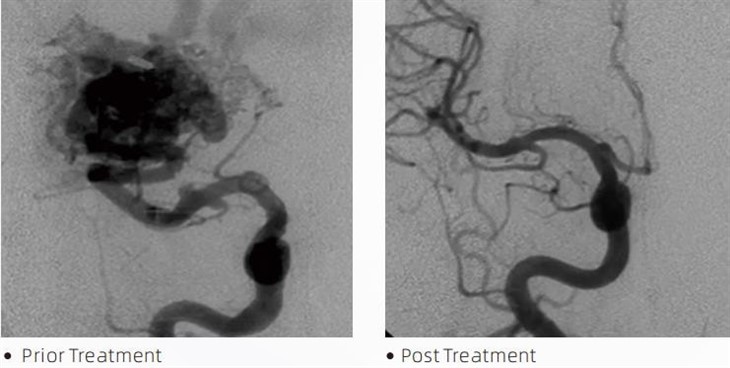

ЛаваТМемболичното лепило е медицинско изделие, използвано от интервенционални неврорадиолози по време на минимално инвазивни процедури за лечение на състояния като церебрални аневризми, артериовенозни малформации и тумори. Лепилото Lava embolic предлага множество предимства както за медицински специалисти, така и за пациенти по отношение на безопасност, лекота на използване и ефективност. Лавата е в състояние да запечата кръвоносните съдове бързо и ефикасно. Процесът включва инжектиране на лепилото директно в целевия съд, където то се полимеризира и втвърдява в подобна на отливка маса, която изпълва аневризмата или малформацията. След това ефективно прекъсва притока на кръв към лезията, предотвратява разкъсването й и намалява риска от трайно увреждане или инсулт. Лавата включва Lava-12, Lava-18 и Lava-34. Всяка формулировка е предназначена да отговори на специфични клинични нужди. Lava-18 е стандартна формула за обща употреба. Lava-34 е лепило с висок вискозитет за съдове с голям поток. Докато Lava-12 има по-нисък вискозитет и е по-течлива, което позволява дистални микросъдове. С тези опции интервенционалните неврорадиолози могат да изберат подходящите Lava формули, за да осигурят оптимални резултати. Една от най-забележителните характеристики на Lava са нейните незалепващи свойства. Това вещество е специално формулирано, за да остане стабилно, докато достигне целевата зона. Тази характеристика означава, че емболичното лепило Lava може да бъде точно поставено в артерията и да остане там, без да залепва или да се свързва с околната тъкан.